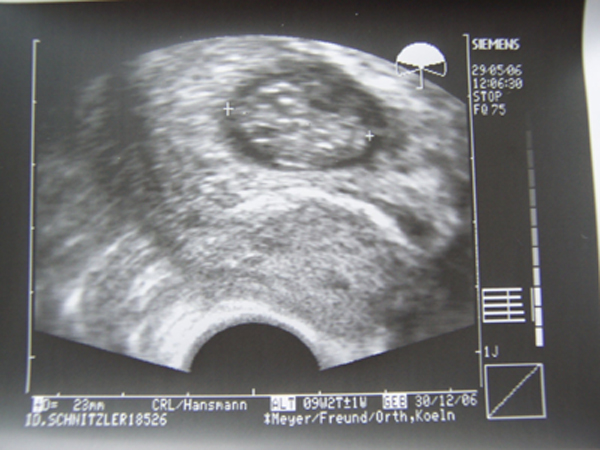

Hatte ja richtig muffensausen vorm US und als meine FÄ den gemacht habe, habe ich am Anfang nichts gesehen und da ist mein Herz gleich noch tiefer gerutscht und dann haben wir unsere Schneeflocke gesehen und eindeutig größer geworden

Hat die ganze Zeit nur geturnt, gewunken, am Daumen gelutscht und meine FÄ hatte Schwierigkeiten zu messen

Nackenfalte ist auch unauffällig, Gehirnhälften waren auch alle zu sehen, ebenfalls war soweit sie sehen konnte bei den inneren Organen alles OK

kein offener Rücken und auch Wirbelsäule sah gut aus.